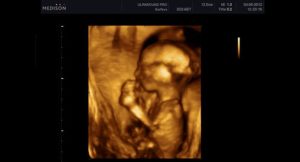

3d узи 14 недель

Многие будущие мамы предпочитают пройти 3д-сканирование – его принцип основан на таком же способе, как и обычное УЗИ, однако трехмерное изображение позволяет выявить пороки сердца и аномалии развития центральной нервной системы. Качественный снимок УЗИ в 14 недель позволяет разглядеть пропорциональное тело крохи, намечающийся волосяной покров на головке, брови и реснички, заметить выражение личика крохи и сходство с родителями.

Но отличаться 3д картинка от 2д будет существенно. На рисунке показаны примеры в двух режимах ультразвукового сканирования.

Рисунок 2. 3д

хорошо определяются структуры лица

Как видно на приведенных выше примерах, изображение при двухмерном сканировании плоское, а разобрать детали на нем может только опытный профессионал. При трехмерном картинка больше напоминает своеобразное «фото» малыша.